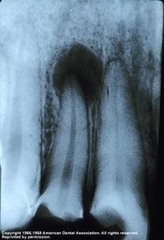

internal resorption

-round to ovoid radiolucency in the central part of the tooth -chronic inflammation -may see pinkish hue to crown if it is involved